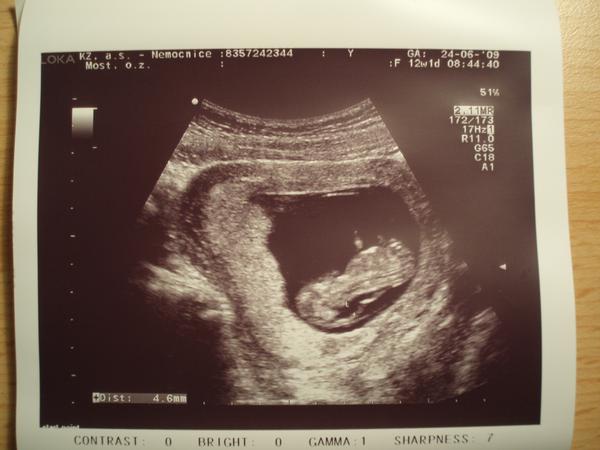

@ivcula7 ve 4 a 5 měsíci je mimčo už velké, to pak se dělá klasickým porodem. ALe nešil. Vždyt ještě nemáš nic potvrzené. 4etla jsi celou diskuzi? já jsem tu jeden čas sepisovala všechny výsledky. zkusím najít poslední soupis. Jo a hodím ti sem foto naší Adélky, kde je vidět jak měla prosáknutí v záhlaví, neboli velké šíjové projasnění, neboli NT. Ne jednom vidíš dole údaj dokonce 5mm. to je délkamezi těmi dvěma body na fotce, jak to doktor měřil. Něco takového viděl i u tebe, že?

@klara.t : NT 4,6, nosní kůstka přítomna, odběr chor.klků - genetika v pořádku, krev v pořádku, UTZ v 16. týdnu v pořádku, velký UTZ v 20.týdnu v pořádku - holčička , kardiologie-podezření na nedomykavost trojcípé chlopně, ale málo významné, na další kontole - srdíčko se umoudřilo, nedomykavost se sama spravila, UTZ v 31+1 v pořádku, 1.1. 2010 se narodila Adélka (3290g, 49cm) - zdravá a v pořádku, kontrola srdíčka - naprosto v pořádku

@lucida : NT 4,6 má zdravou holčičku

@olga777: NT=4,6 (12tt), UTZ OK

Mě tenkrát doktor říkal, že NT do 6 je v pohodě. Stejně mě neuklidnil a začala jsem pátrat na netu po informacích. A našla jsem tyto stránky a ponořila se do toho problému víc a víc (u dcery jsem ani nevěděla, že nějaké NT hodnoty existují a měla 3,5. A byl klid). U syna by mi doktor ani ty NT(4,6) hodnoty neřekl, kdybych se nezeptala. Tenkrát mě naštval a odešla jsem od něj 🙂